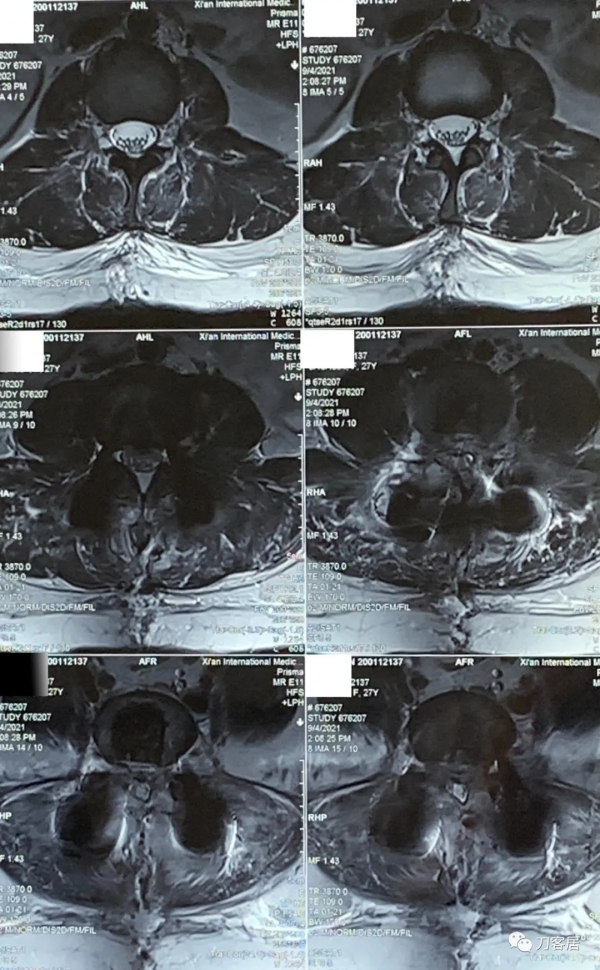

圖5. 20210817術前腰椎MRI橫截面掃描提示L3-4椎間盤輕度突出,左側旁中央型。

圖6. 20210817術前腰椎MRI橫截面提示L4-5椎間盤突出,較大,右旁側型。

圖7. 20210817術前腰椎MRI橫截面掃描,提示L5-S1椎間盤突出,右旁中央型。